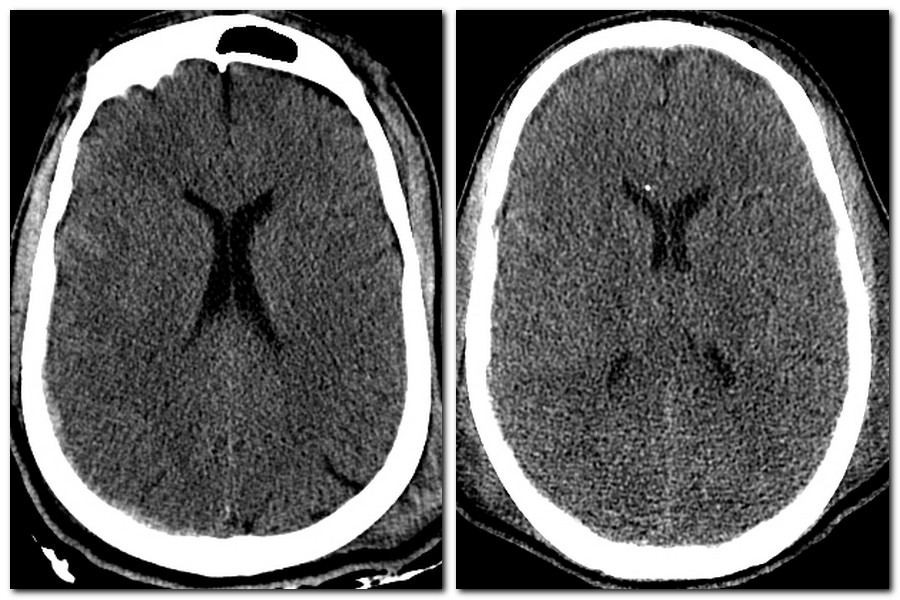

- Genetic Determinants of Post-traumatic Cerebral Edema

Genetic Determinants of Post-traumatic Cerebral Edema

Objectives: To investigate whether there are genetic determinants of post-traumatic edema, in particular, the AQP4 and CACNA1 gene mutation.